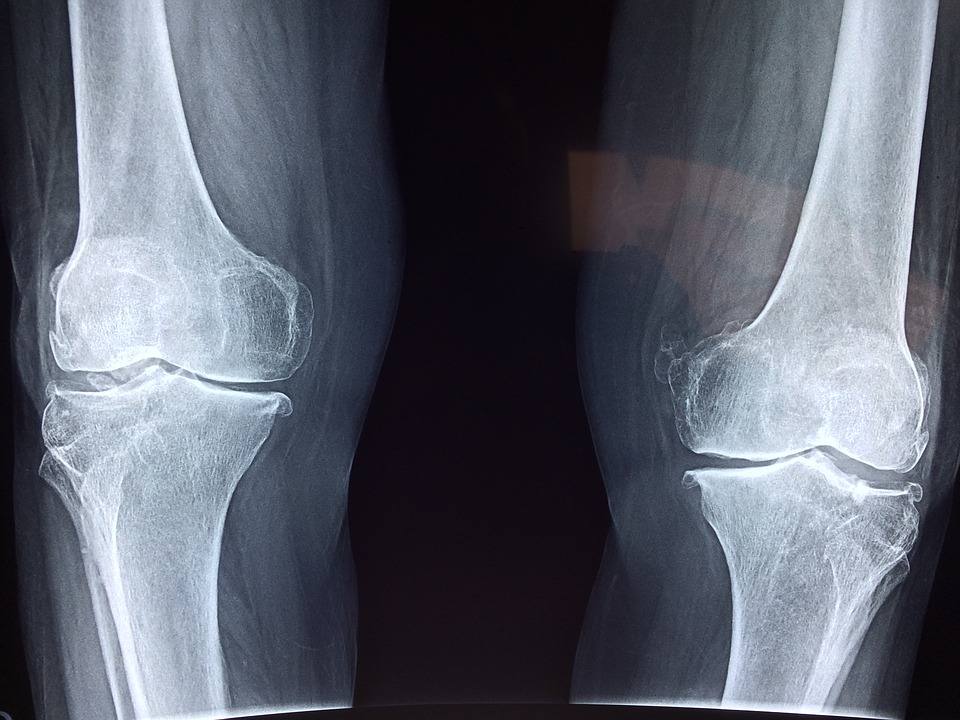

โรคข้อเข่าเสื่อม ( Osteoarthritis )

ภาวะที่กระดูกอ่อนผิวข้อเข่ามีการสึกหรอรวมถึงเสื่อมอย่างช้าๆ และเริ่มแสดงอาการมากขึ้นตามเวลาที่ผ่านไป โดยพบมากในผู้สูงอายุ หรือคนที่ใช้ข้อเข่าหนักๆ เมื่อเกิดอาการจะมีลักษณะปวดเข่า เข่าบวม มีเสียงดังกรุ๊บๆในข้อเข่า โรคข้อเข่าเสื่อมมักเกิดตามข้อต่อใหญ่ๆเช่น ข้อสะโพก ข้อเข่า และ ข้อกระดูกสันหลัง โรคข้อเข่าเสื่อมพบมากในผู้สูงอายุเพศหญิงมากกว่าเพศชาย